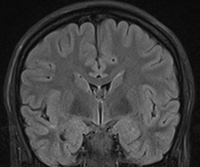

Den superiore flade af temporallappen grænser op mod Insula inferiore halvdel. Den forreste del af denne flade er konkav (planum polare) og matcher den anteriore inferiore konvekse form af Insula, mens den posteriore supriore flade en med plan (planum temporale). Denne forskel kan tydligt erkendes på coronale MR-skanningssnit (Fig. 5+6). Overgangen mellem den konkave og den plane den af temporallappens superiore flade markere lokalisationen af Heschel's gyrus. Heschel's gyrus har et skråt forløb fra antero-lateralt til postero-medialt. Lateralt findes Heschel's gyrus lige overfor gyrus postcentral i parietallappen adskilt af lateralfissuren. Følges Heschel's gyrus medialt posteriort peger den mod atrium af ventrikelsystem lige posteriort for thalamus (Fig. 4).